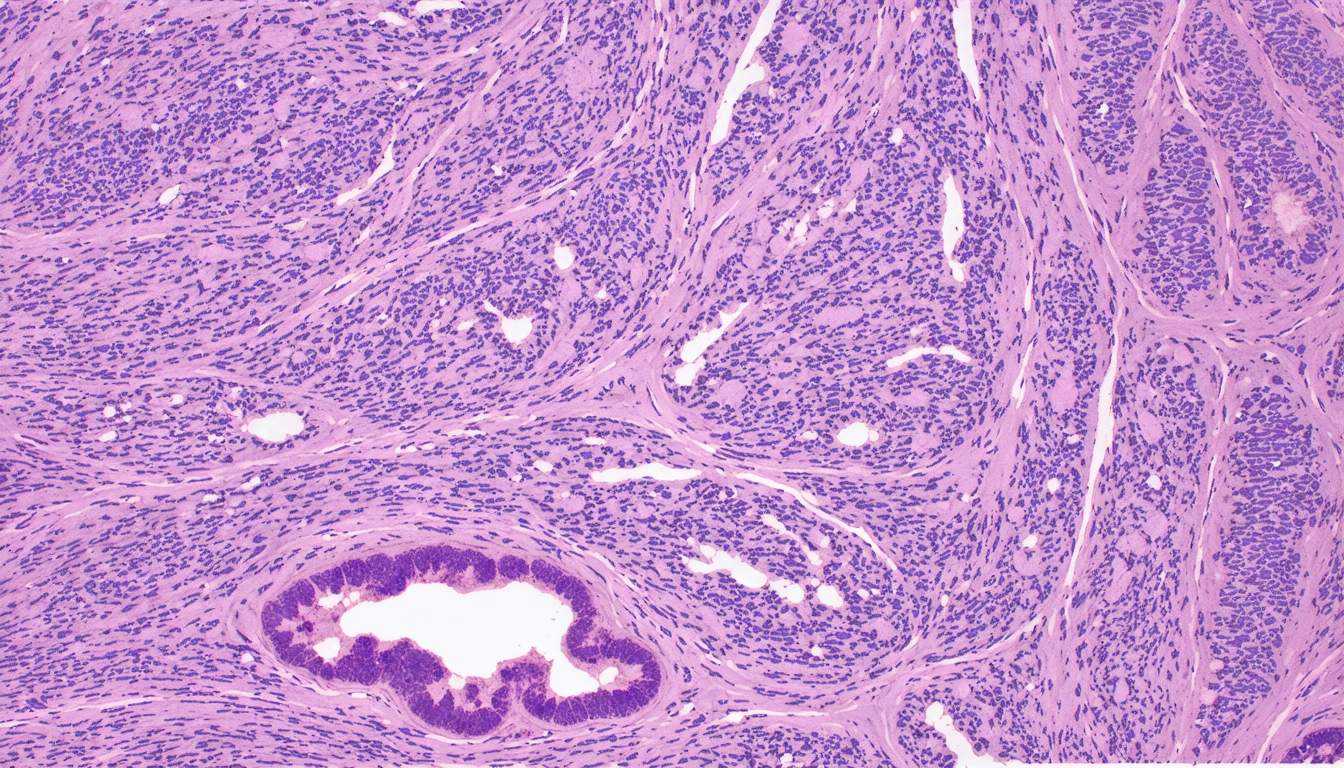

Amyloidosis refers to a group of disorders characterized by extracellular deposition of abnormal amyloid protein. These proteins form beta-pleated sheets, leading to dysfunction in affected tissues.

- Staining Techniques: Amyloid deposits exhibit apple-green birefringence under polarized light when stained with Congo red.

- Types of Amyloid: Different forms include AL (light chain), AA (reactive systemic), ATTR (transthyretin-related), and Aβ (associated with Alzheimer's disease).

- Organ Involvement: Commonly affected organs include kidneys, liver, heart, and nervous system.

Histological examination using Congo red, electron microscopy, and immunohistochemistry can help confirm amyloidosis.